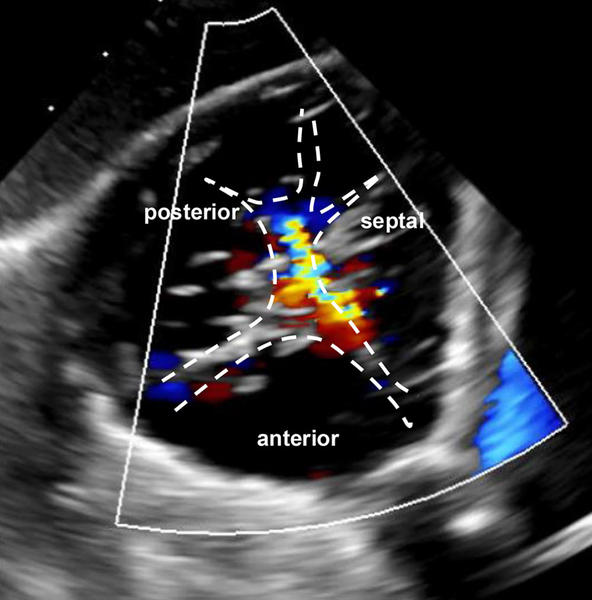

Das Herzteam evaluierte zudem die aus der Echokardiographie abgeleitete Morphologie der Trikuspidalklappe, und stufte sie gemäß Hausleiter J et al. (JACC 2025) in die Gruppe der für T-TEER geeigneten Anatomien ein, basierend auf den folgenden Fallkriterien:

- Torrentielle funktionelle TI mit septolateraler Koaptationslücke ≤ 7 mm

- Regurgitationsjets: anteroseptal und posteroseptal

- Morphologie der Klappen: geeignet, mit identifizierbaren Segmentierungen der hinteren und septalen Klappen

- Clover-Technik: Das erste Device wird anterior-septal, das zweite posterior-septal implantiert, um beide Regurgitationsjet zu behandeln